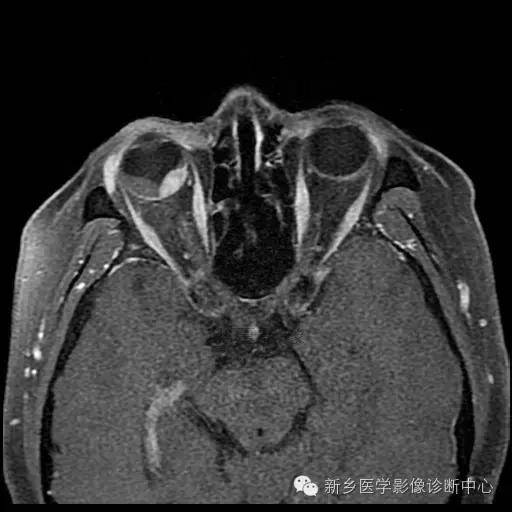

黑色素瘤,为何被称为“不治之症”?什么是黑色素瘤? 黑色素瘤,通常是指恶性黑色素瘤,是黑色素细胞恶变而来的肿瘤,在皮肤肿瘤中恶性程度最高,它多发生于皮肤,也可以发生于黏膜(包括内脏黏膜)。我国皮肤黑色素瘤患者多发生在肢端皮肤(包括足底、手指末端、指/趾甲下等),可由色素痣恶变而来。 哪些危险因素容易导...